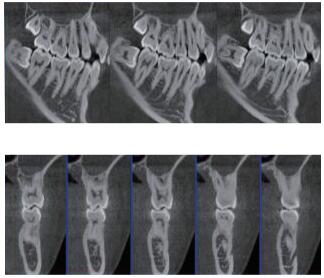

專有三維重建算法,可提供任意位置高清斷層影像。

高清口腔全景影像

通過三維容積影像,提取高清口腔全景影像。